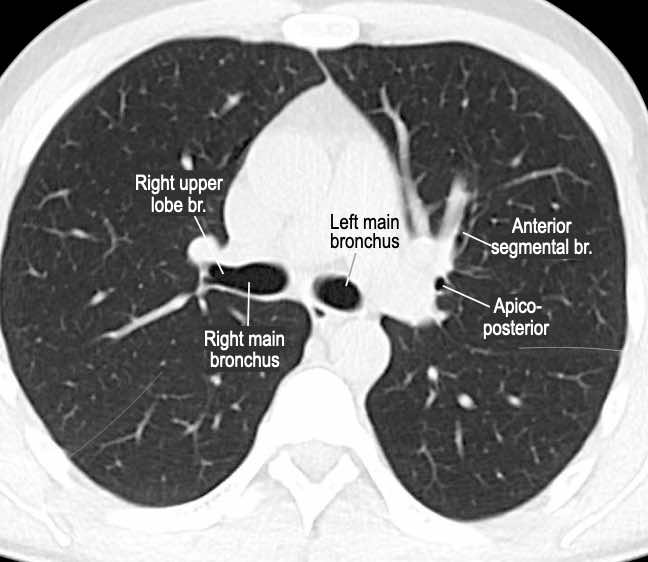

Phế quản trên CT

Cuộn qua các hình ảnh để quan sát khí quản phân chia thành phế quản chính phải và trái, sau đó tiếp tục phân chia thành các phế quản thùy và phế quản phân thùy.